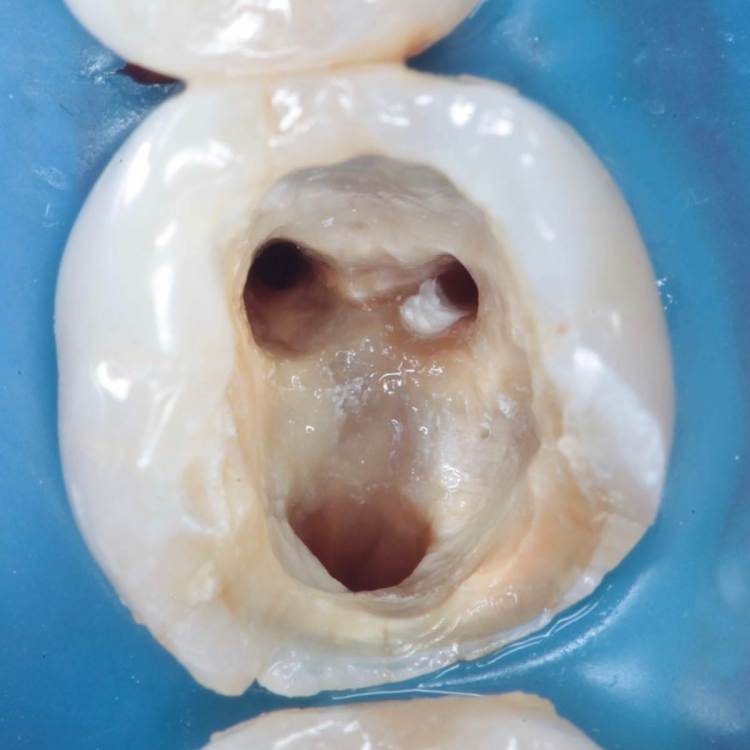

Как эта перфорация образовалась история умалчивает, оно и не важно, и так видно. Асимметричное расположение корневых каналов всегда наводит на мысли о неправильно раскрытом устье.